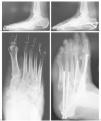

La reconstrucción del tobillo en la artropatía de Charcot, que con frecuencia se realiza tras un traumatismo, se indica ante la aparición de úlceras e inestabilidad. Una fijación rígida se obtiene mediante tornillos a compresión y en ocasiones con una placa condílea o un clavo intramedular retrógrado. Este último se emplea principalmente en casos de fractura luxación de tobillo o del retropié, aunque los autores prefieren los tornillos largos de 6,5 mm o tipo bolt porque proporciona un mejor control de la rotación y mantiene una mejor reducción (fig. 2).

Figura 2. A: visión posterior de un paciente de 46 años de edad con diabetes mellitus tipo 1 y un pie de Charcot. Presenta una importante deformidad y tumefacción a nivel del retropié. B: proyección radiológica lateral que muestra la luxación lateral del calcáneo bajo el peroné. La tibia se articula con el cuerpo y cuello del astrágalo parcialmente desintegrado, y se aprecia inestabilidad de la articulación de Chopart y colapso de la columna medial. C: se realizó un alargamiento del tendón de Aquiles y se utilizó un fijador externo híbrido para realizar distracción y conseguir la reducción del calcáneo bajo el astrágalo. Los pines se colocaron en la tibia proximal, la tuberosidad posterior del calcáneo y los huesos del tarso. D: una visión anteroposterior del tobillo confirma la reducción del calcáneo bajo el astrágalo y la desintegración del maléolo peroneal. E: proyección lateral en la que se observa la reducción del tobillo inestable y del retropié, con una doble fusión que se extiende a la articulación de Chopart, la columna medial y la articulación de Lisfranc. Se empleó aloinjerto de banco para rellenar los defectos. F: una proyección oblicua muestra la extensión de la fusión al tobillo previa osteotomía del peroné para acceder a dicha articulación. El alineamiento y la estabilidad mejoraron. G: visión posterior del pie y del tobillo tras la reconstrucción con un ligero valgo residual. El paciente está ahora andando con una plantilla doble (insert) y calzado con suela de balancín sin muletas, y se ha incorporado a su trabajo habitual como empleado de banca.